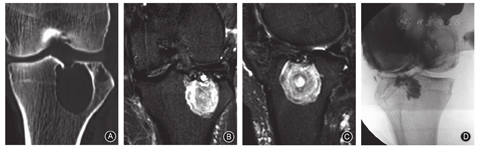

本组1例膝关节腔内色素沉着绒毛结节性滑膜炎患者,关节镜术后3年出现复发,CT扫描示胫骨近端近髁间隆突处骨质破坏,MRI示胫骨近端近髁间隆突处肿瘤占位,与关节腔交界处存在"瘤蒂",第2次关节腔切开清理术前,向关节腔注入碘海醇,"C"型臂X线机透视造影剂自隆突中凹部孔道所在位置向胫骨近端瘤腔渗入(图5)。

1例胫骨近端骨巨细胞瘤,患者术前CT扫描示瘤腔与"胫骨髁间隆突孔"相通,行刮除植骨+骨水泥填充术,术后6个月复发,复发后CT扫描示肿瘤由髁间突入关节腔(图6)。